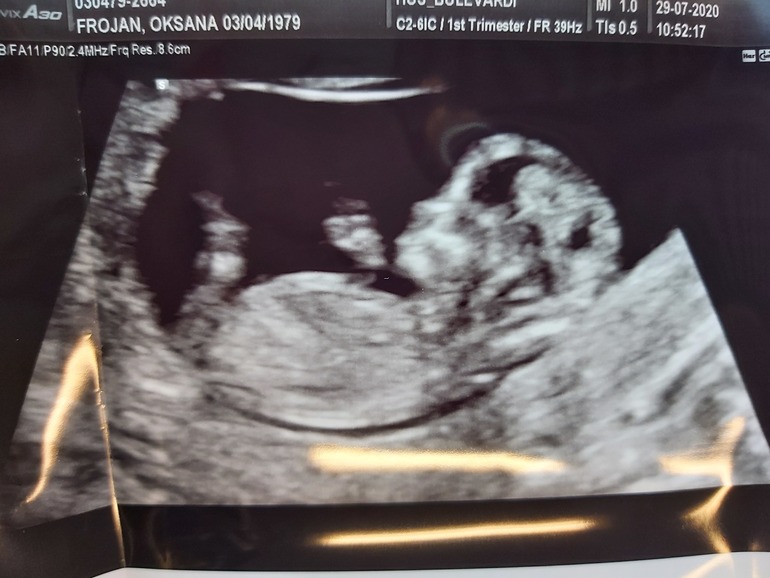

Свершилось! Долгожданный первый скрининг! Наконец-то я услышала,как бьётся сердечко нашего малыша!😍 До сих пор не верится,что внутри меня кто-то живёт 🤣🤭 Анализы все в норме,слава богу,никаких отклонений нет. Сдвинули срок на три дня раньше-по месячным было ровно 12 недель в среду,поставили 12+3. Рост у нас 59 мм,шея 1,2,нос паааапин,армянский видимо будет 🤣🤣. Пыталась разглядеть,кто там ,но ребенок так вертелся, прыгал и скакал,что еле померить удалось))) поэтому пол пока загадка... Сегодня устраиваем ужин и будем сдаваться родителям😁 ...

а может кто сумеет нам пол предсказать по фоткам?;)